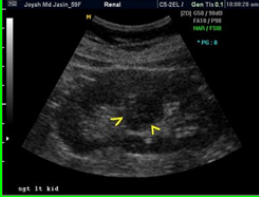

Double Collecting System (aka Duplex Kidney)

Duplication of collecting system - may be complete (2 ureters) or incomplete (1 ureter).

image of duplex kidney

sonographically of duplex kidney

Band of cortical tissue seen throughout a mid area section of the kidney that can be seen in both long and trans.